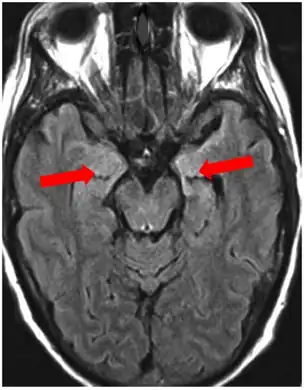

Image of limbic encephalitis (and positive NMDAR antibodies in the CSF)- increased signal intensity is seen in the bilateral medial temporal lobes and hippocampi.

Neuroimaging

Brain MRI is the mainstay of initial investigation pointing to limbic lobe pathology revealing increased T2 signal involving one or both temporal lobes in most cases.[22][14]

Serial MRI in LE starts as an acute disease with uni- or bilateral swollen temporomesial structures that are hyperintense on fluid attenuation inversion recovery and T2-weighted sequences. Swelling and hyperintensity may persist over months to years, but in most cases progressive temporomesial atrophy develops.[23]